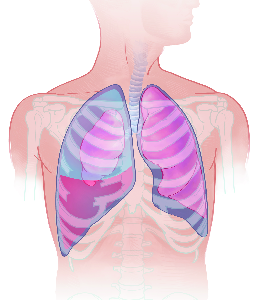

Detailreiche Fotografien aus der medizinischen Praxis ergänzen die Texte; moderne, genaue,

wissenschaftliche Zeichnungen geben Einblick in die Anatomie und die Funktion der Lunge und

anderer Organe.